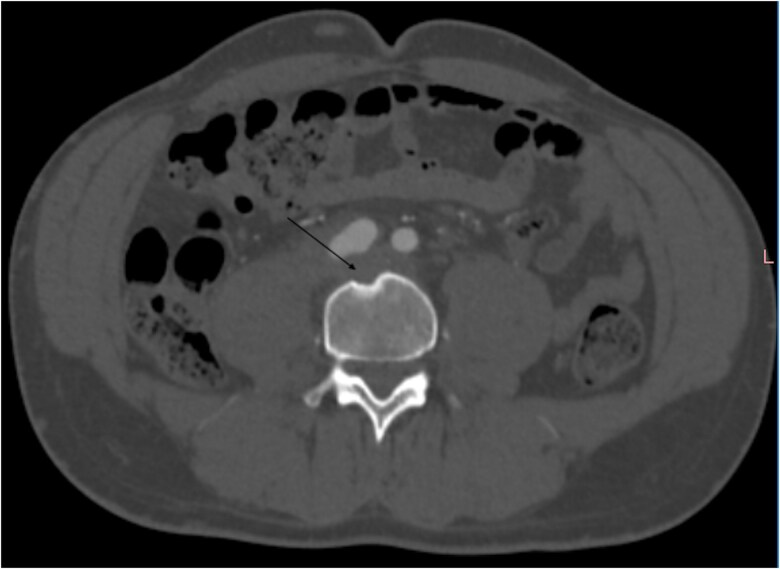

相对罕见的髂总动脉动脉瘤是血管的异常扩张,在罕见的情况下,可能会因破裂而复杂化,破裂可能被周围的结构所包含。影像学,特别是CT血管造影,在诊断中起着关键作用。我们报告一例包含破裂的髂总动脉瘤负责肾积水,髂总静脉阻塞,和邻近椎体的溶解。

Relatively rare aneurysms of the common iliac artery are abnormal dilatations of the vessel, which can be complicated by a rupture that, in rarer cases, may be contained by surrounding structures. Imaging, particularly CT angiography, plays a key role in diagnosis. We report a case of a contained rupture of the common iliac artery aneurysms responsible for hydronephrosis, obstruction of the common iliac vein, and lysis of the adjacent vertebra.